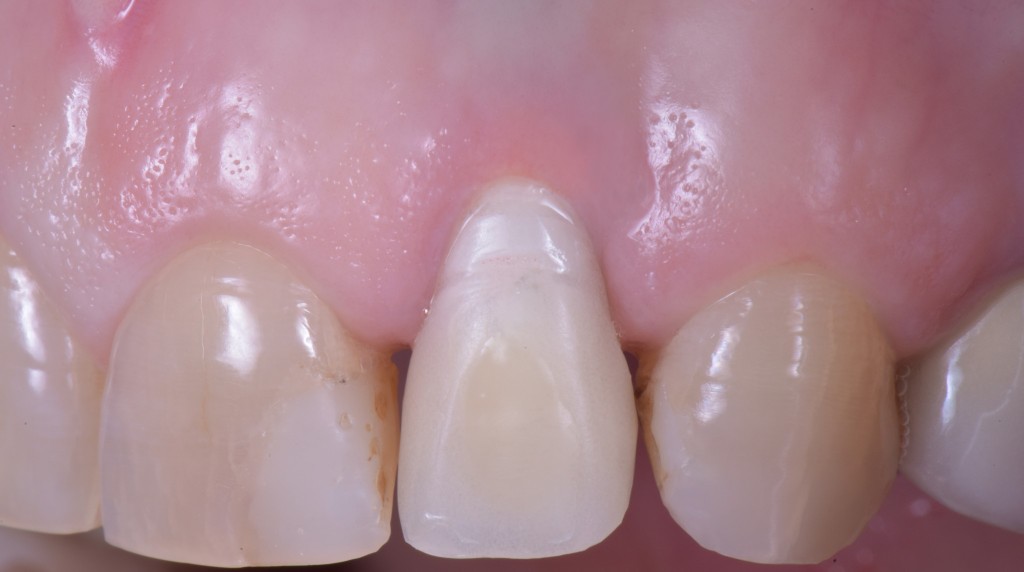

O questo, se vuoi un esempio frontale.

gestione dei tessuti molli - esempio frontali